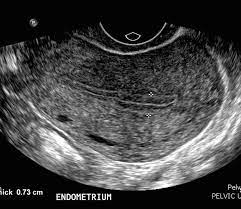

Penebalan dinding rahim membuat sulit hamil? Beberapa yang bisa menjadi indikator adalah: Haid lebih lama dengan volume darah yang juga lebih banyak. Karena pembesaran dan penebalan rahim itu tidak selalu menjadi ciri anda hamil ya. Hormon ini melenturkan leher rahim pada akhir kehamilan, sehingga bayi lebih mudah untuk keluar. Saat hasil test pack menunjukkan garis dua, yang segera dilakukan calon ibu baru adalah mengunjungi dokter sesegera mungkin. Sebenarnya, penebalan dinding rahim bukan suatu aktivitas dari kanker. Wanita yang sedang hamil muda biasanya mengalami kenaikan suhu tubuh sedikit di atas ambang normal, namun tidak sampai demam. Jika endometrium terlihat tebal, maka bisa saja hal ini menujukkan bahwa adanya penebalan dinding rahim, hiperplasia endometrium. Tanda tanda penebalan dinding adalah sebagai berikut. Simak penyebab dan gejala lainnya disini yuk! Cara menyembuhkan penebalan dinding rahim secara total cara menyembuhkan penebalan dinding rahim secara total paling ampuh terbukti sembuh total hanya dengan gamat emas kapsul yang sudah banyak terbukti menyembuhkan penebalan dinding rahim secara total dengan proses alami, aman dan tanpa efek samping selain itu juga sudah banyak kesaksian kesaksian konsumen kami yang sudah merasakan kesembuhan … Apakah siklus menstruasi ibu teratur atau tidak?.

Penebalan dinding rahim perlu diobati terlebih dahulu untuk memulai program hamil. Penebalan dinding rahim ini biasa disebabkan akibat. Artinya, risiko kanker rahim atau operasi pengangkatan rahim bisa dihindari. Jika akan haid dinding rahim memang menebal, dan tp yg samar pun terkadang menandakan akan haid atau hamil. Ketebalan dinding rahim berubah selama siklus menstruasi. Penebalan dinding rahim bisa terjadi akibat melonjaknya hormon estrogen dalam tubuh. Pastikan mama waspada terhadap setiap gejalanya, ya. Bisa saja masalah ini dapat sembuh sendiri tanpa perlu diobati.

Estrogen bisa meningkat karena dipicu oleh pertumbuhan kista. Penebalan dinding rahim bisa terjadi akibat melonjaknya hormon estrogen dalam tubuh. Sebenarnya proses kuret tak memakan waktu yang lama. Namun untuk lebih memastikan apakah anda hamil atau tidak maka anda harus mengetesnya dengan tespeck atau tes ke dokter kandungan. Peluang terbaik untuk hamil yang sehat itu kalau endometrium memiliki ukuran yang pas. Penebalan dinding rahim, bahasa kedokterannya hiperplasia endometrium, dapat menjadi penyebab pendarahan menstruasi yang tidak normal. Haid lebih lama dengan volume darah yang juga lebih banyak. Namun, banyak pula kondisi yang dapat menyebabkan perdarahan abnormal.